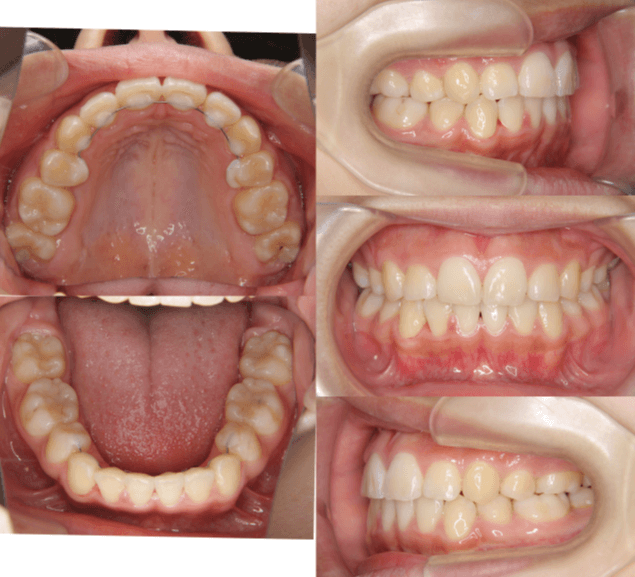

| 年齢・性別 | 8歳9ヶ月の女児 |

|---|---|

| 主訴 | 歯並びの乱れを気にされて来院された患者様です。将来的なスペース不足と歯のねじれ(翼状捻転)が懸念されました。 |

| 治療期間・回数 | 2年10ヶ月・19回 |

| 費用 | 430,000円(税別) |